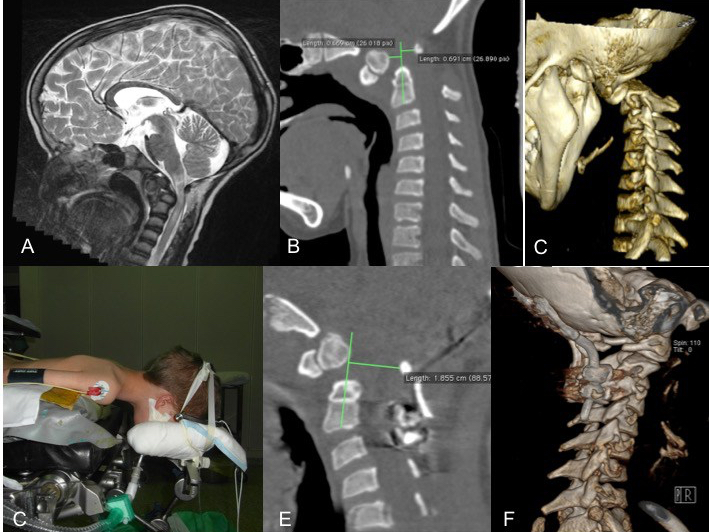

A os odontoideum dans la trisomie 21 avec dislocation C1-C2 ; B traction par étrier de Gardner ; les billots supportent les vis de l’étrier pour éviter l’appui occipital avec risque d’escarre ; C réduction montrant la grande instabilité de la lésion ; noter que le point d’application de la traction imprime un vecteur en lordose. - halo-veste : posé au bloc sous AG ; le couple de torsion idéal des vis est de 2N.m ; il est moindre chez les petits. le nombre de vis nécessaire est donc inversement proportionnel à l’âge du patient

- peropératoire par mise en traction axiale, et engagement des vis occipitales dans les gorges permettant une rétropulsion du crâne par rapport au rachis